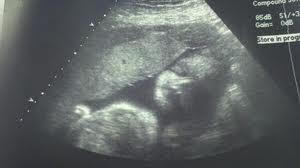

Semana 30 de embarazo.

El niño está formado y podría sobrevivir en el exterior con una serie de cuidados, en las siguientes semanas su función principal será engordar y afinar sus sentidos, órganos y sistemas. El bebé tan solo pesa kilo y medio, con lo que en tan solo 10 semanas doblará su tamaño y lo que ello conlleva tu también engordaras a lo largo de esta última etapa del embarazo.

- El peso del niño está alrededor del 1.5 kilos y llega a una estatura de unos 43 cm.

- En estas semanas la evolución más importante es la de coger peso.